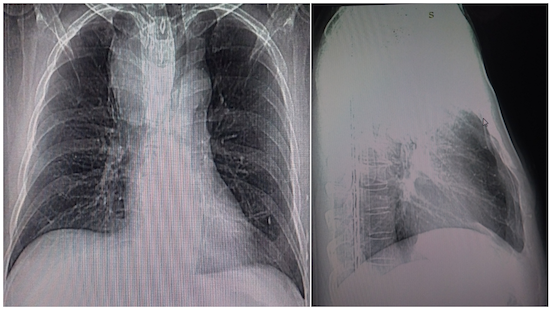

Paciente del sexo masculino de 66 años, con antecedentes de hipertensión arterial para lo cual lleva tratamiento. Que acudió a consulta por presentar decaimiento, cansancio fácil, tos seca de meses de evolución, frecuentes palpitaciones, disfagia y cambios de la voz (ronquera), cuadro que comenzó hacía aproximadamente hace dos años, y fue aumentando en intensidad, sin otras complicaciones. Al examen físico se constató como dato positivo en la exploración del cuello tiroides visible (tiromegalia), palpable a predominio del lóbulo derecho, con adenopatías palpables. El paciente estaba clínica y biológicamente eutiroideo, así mismo las pruebas de laboratorio no mostraron anormalidades y las pruebas de función tiroidea fueron normales. La radiografía de tórax (vista anteroposterior y lateral) se observó ensanchamiento del contorno derecho del mediastino anterosuperior una masa bien delimitada de contornos regulares, bien definidos que provoca desviación de la tráquea hacia la izquierda de la línea media, en la vista lateral se proyecta en un plano medio con desviación y compresión de la tráquea desplazándola hacia delante (Figura 1).

Figura 1. Radiografía de tórax. Proyeccion PA: aumento del diámetro transverso del mediastino superior por radiopacidad redondeada que comprime y desplaza la tráquea hacia la izquierda. Proyeccion Lateral derecha:discreta radiopacidad peri-traqueal en mediastino anterosuperior que sugiere la presencia de una masa mediastínica.